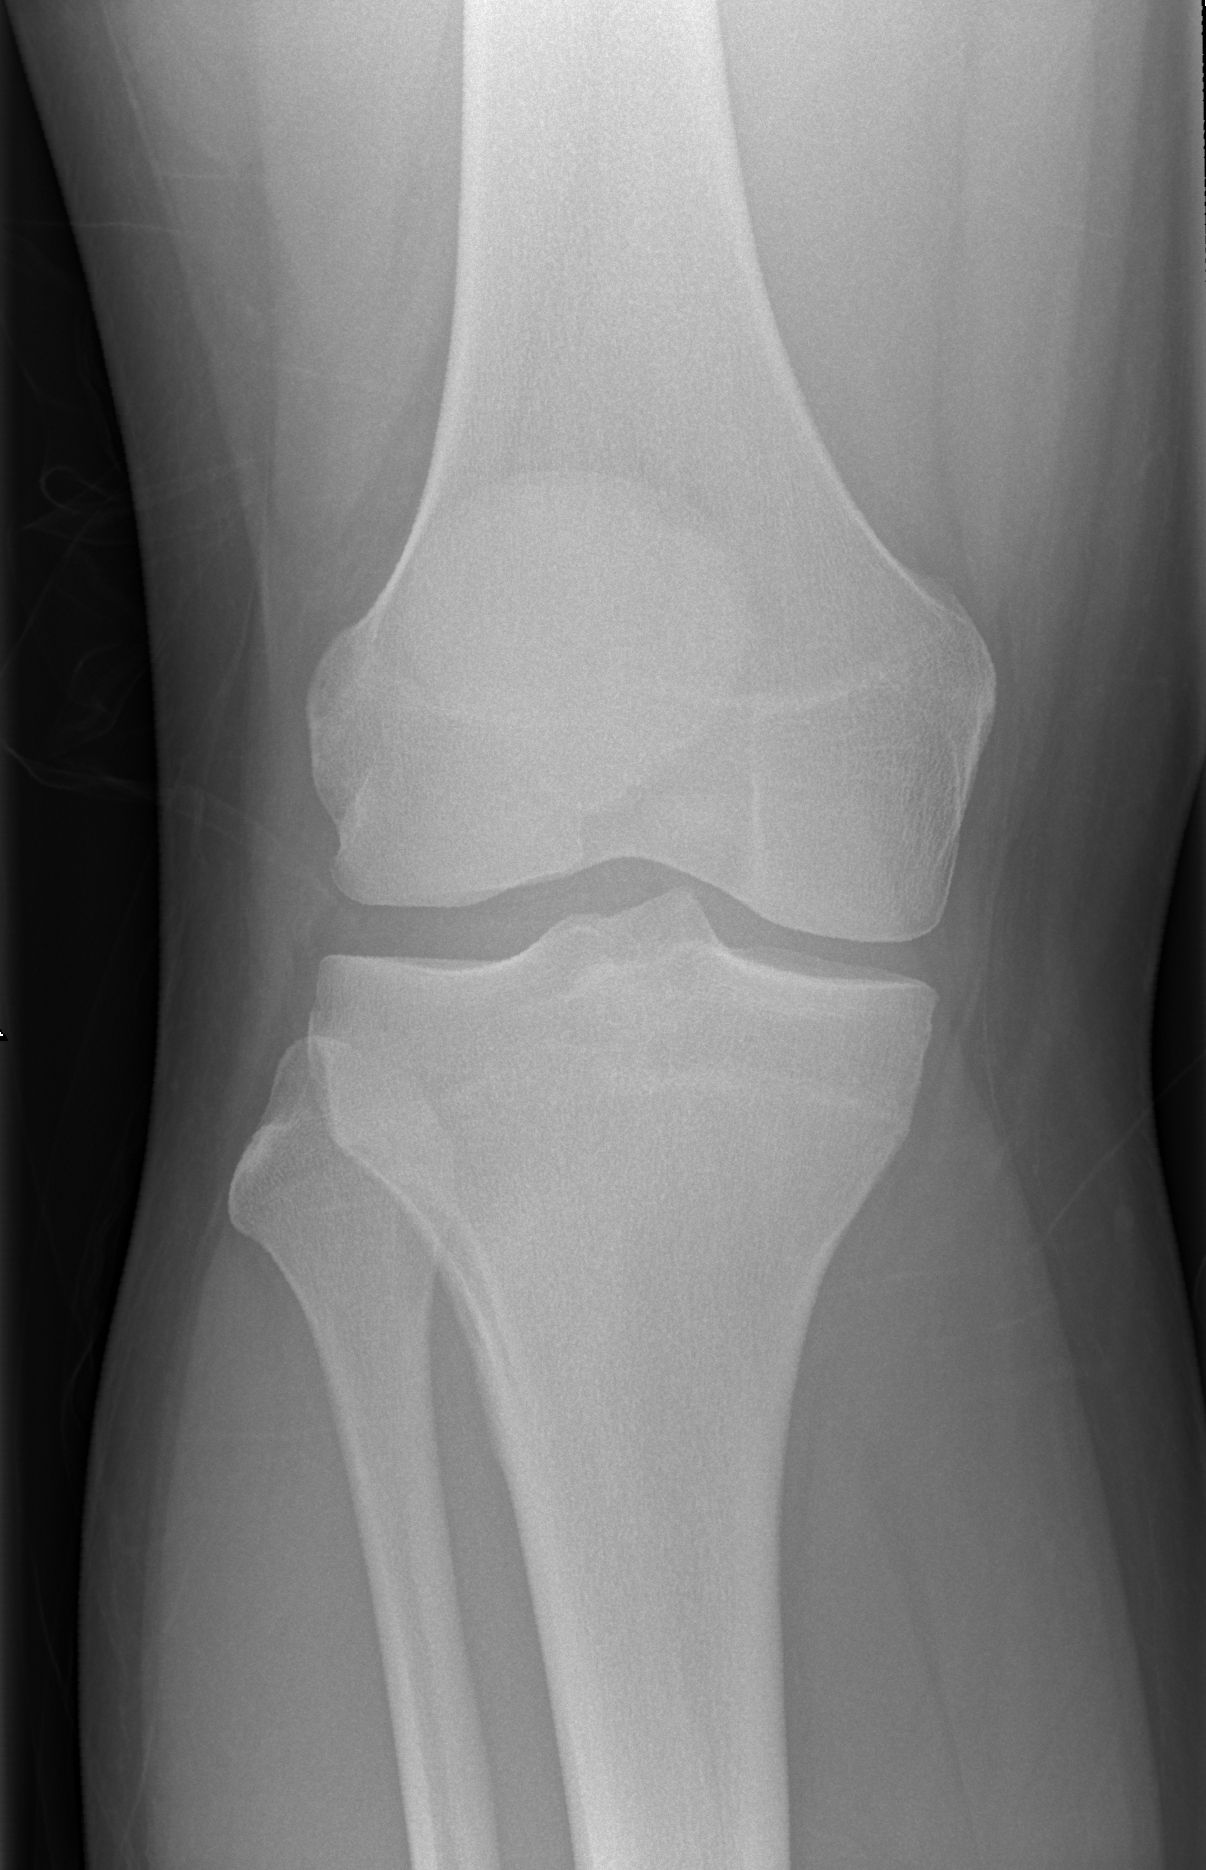

解剖学模块